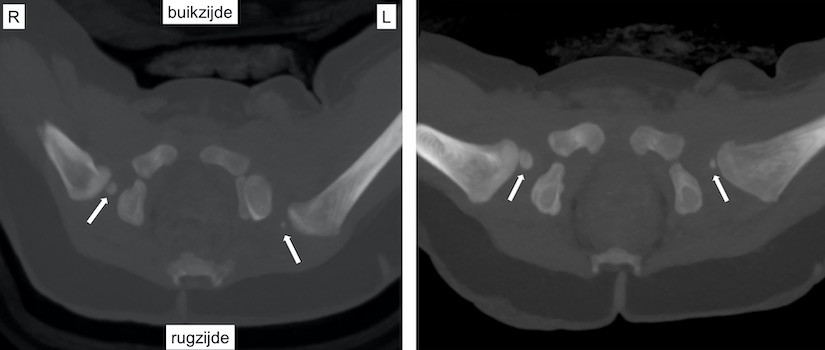

Links: CT-scan van het bekken van een baby van 8 maanden. Dwarsdoorsnede door het heupgewricht. De heupkoppen zijn gemarkeerd met witte pijlen. De linkerheupkop is naar achter (rugzijde) geluxeerd. Dit is op een röntgenfoto niet goed te zien.

Rechts: CT-scan van het bekken van dezelfde baby als figuur 7, 1 maand na repositie. De linkerheupkop staat goed in de kom..

Bij kinderen met heupluxatie kan een CT-scan worden gebruikt om te controleren of de heupkop goed in de heupkom staat als het niet lukt om dit op een andere manier te bekijken.